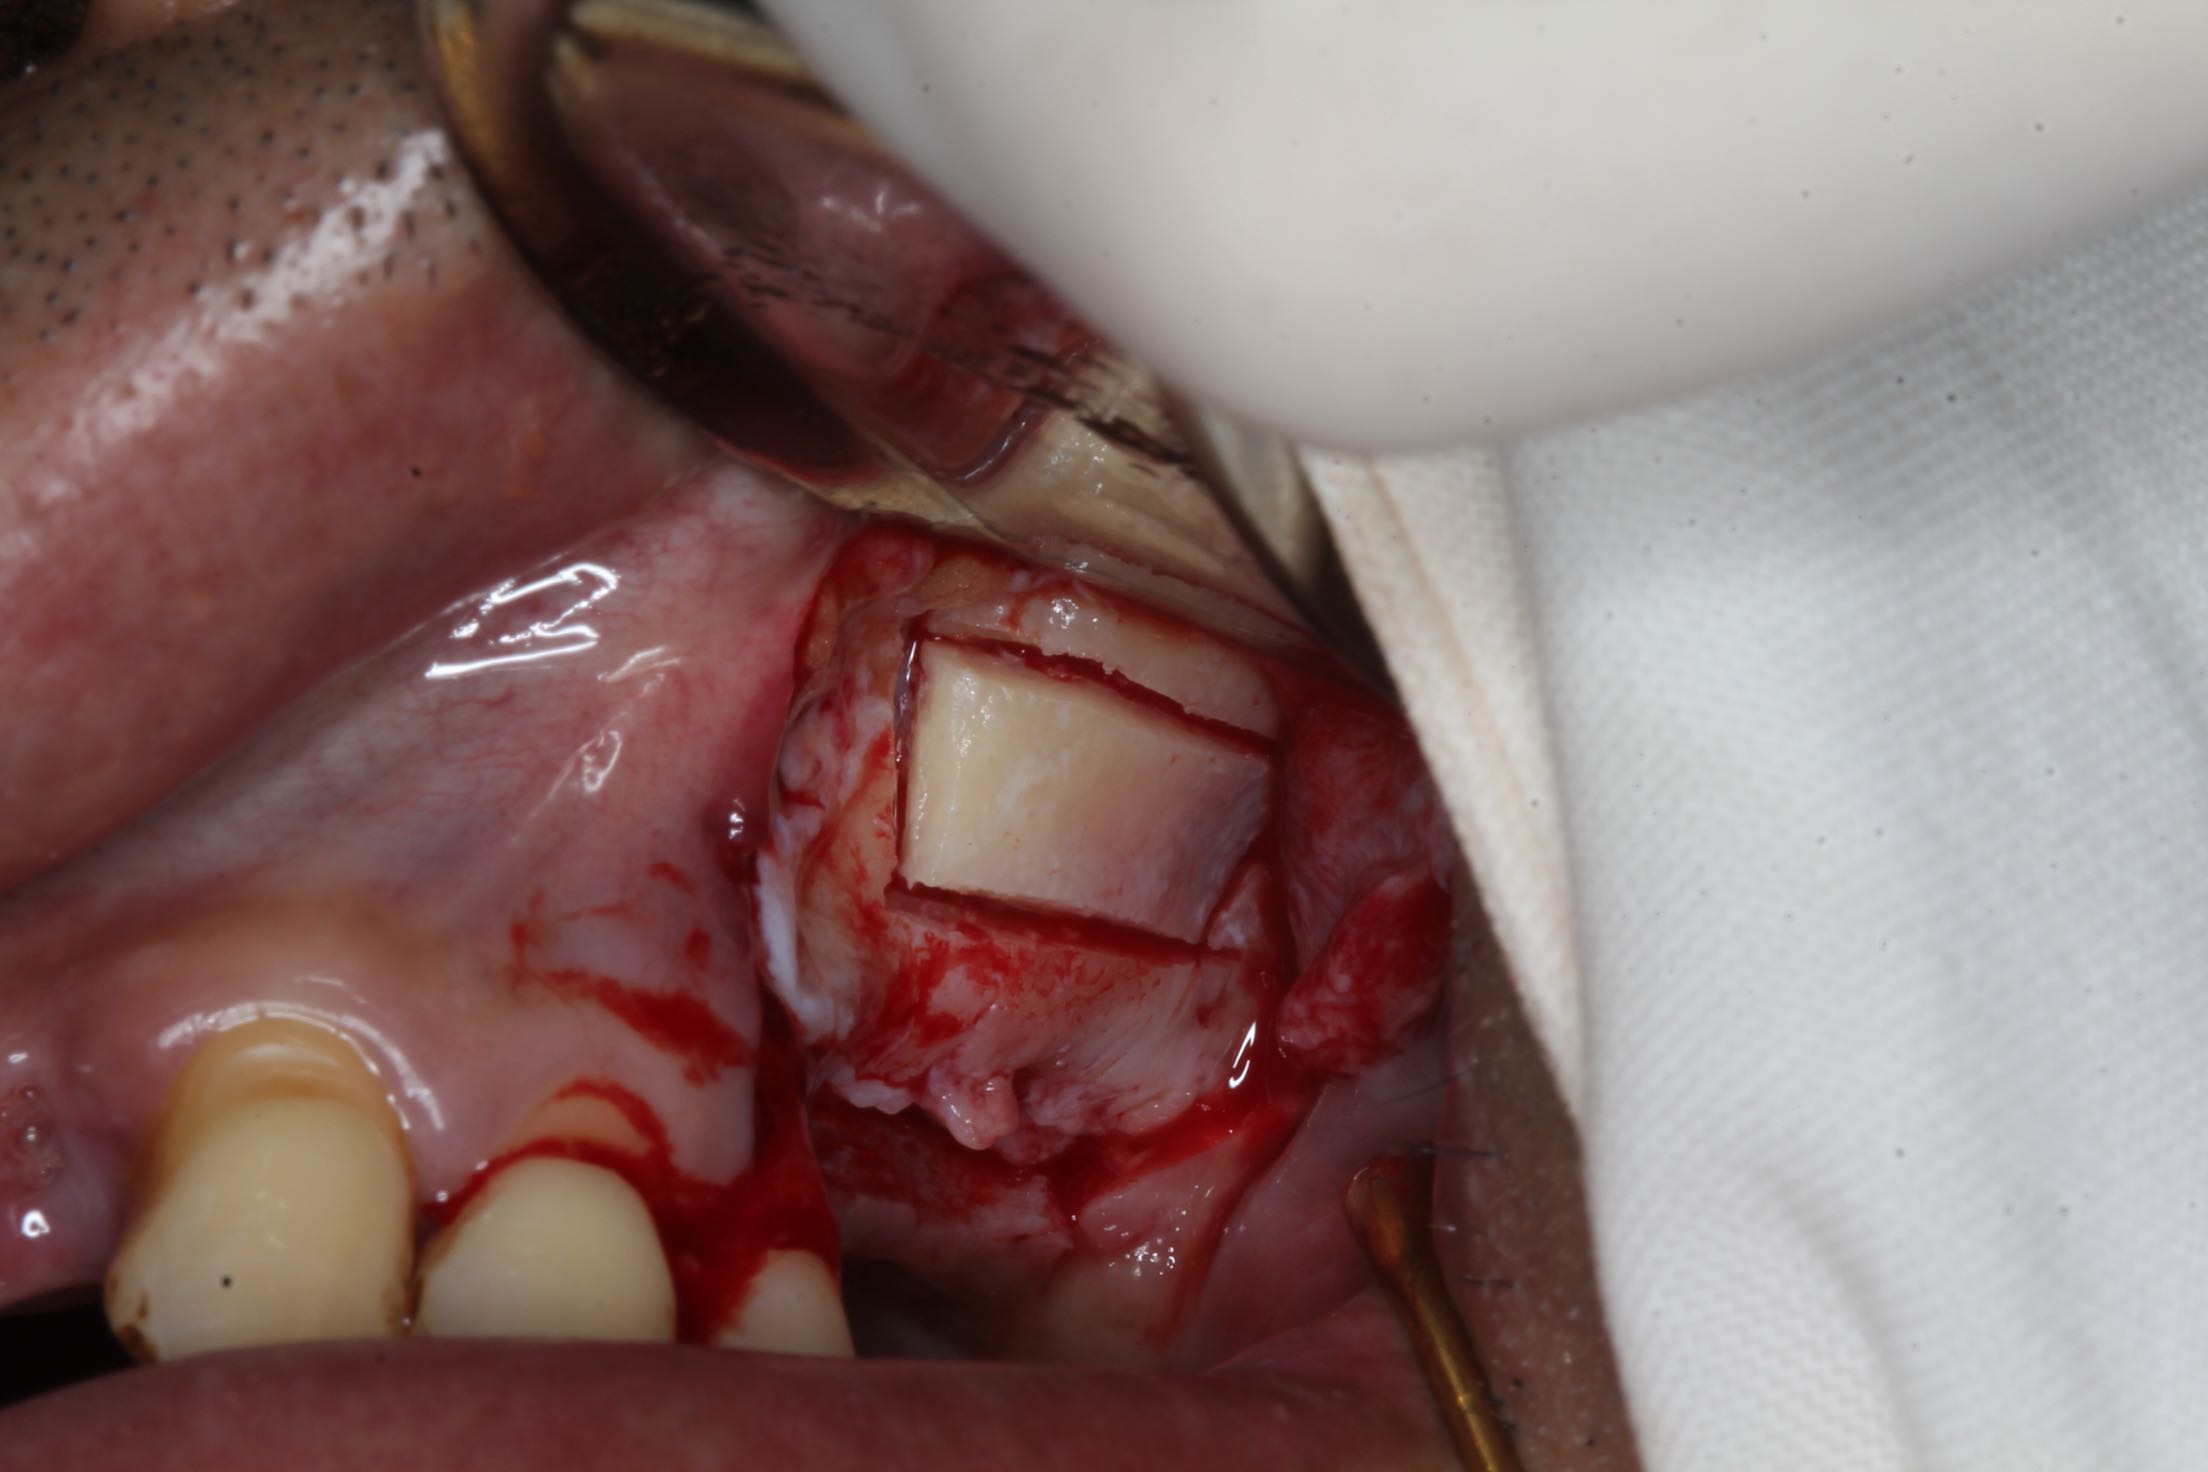

26、27缺失,牙槽骨严重吸收。 治疗:上颌窦外侧壁超刀开窗,取出外侧壁骨块,剥离黏膜,考虑严重吸烟史,黏膜菲薄,垫上一层胶原膜,植入部分Bio-ss骨粉,牙槽嵴顶备洞,26牙植入dentium4.3-10,27牙植入4.3-8,继续植入骨粉共0.5g,开窗处复原骨块,严密缝合!26牙植入扭力35牛,27植入扭力15牛!嘱尽量戒烟,